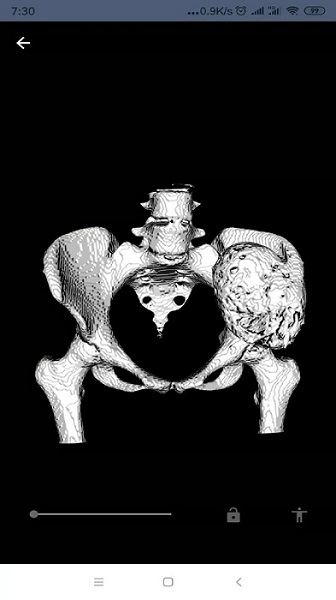

将二维医学影像图片重构成一个三维模型的软件,方便用户更直观观看重构部位。更是更直观的理解医院影的像内容。用户仅需简单的将数据上传至我们的服务器,重建完成后我们将通知您,然后再此软件上进行查看。

重建模型,可以便捷的查看非常形象的可视化三维模型,利于掌握病情;

可以使用户,更加形象查看重构部位。

提供基于ct、mri二维医学影像的三维重建技术服务。

本软件是可以将,医学影像图片,重构成一个三维模型的软件。

三维重建是指对三维物体建立适合计算机表示和处理的数学模型

画质非常的清晰,便于用户根据反馈的三维模型进行详细观察;